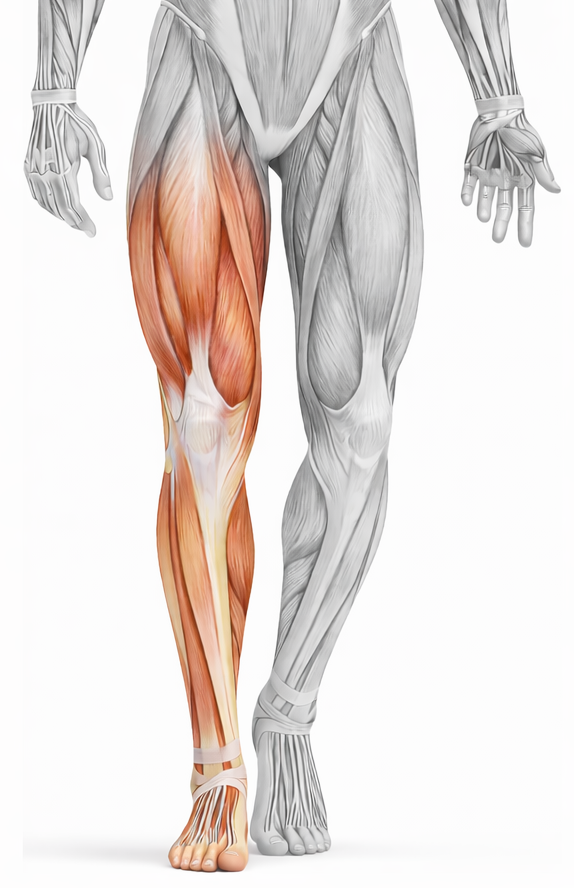

Lower Limb

Learn Gross Anatomy of Lower limb including functional aspects, joints, nerves, vessels, and its clinical aspects.